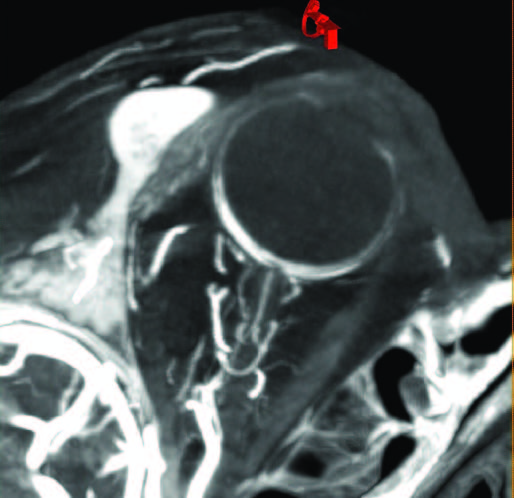

Рис. 2. Интранодальная паховая ПДКТ-лимфангиография с последующей чрескожной пункцией лимфопсевдоаневризмы (толстая красная стрелка) иглой 25 G (0,5 мм) (тонкие желтые стрелки) с целью эмболизации массивной послеоперационной тазовой лимфореи (длинная синяя стрелка): ПДКТ позволяет отчетливо визуализировать пункционную иглу на реконструированных изображениях и точно определить положение ее дистальной части.